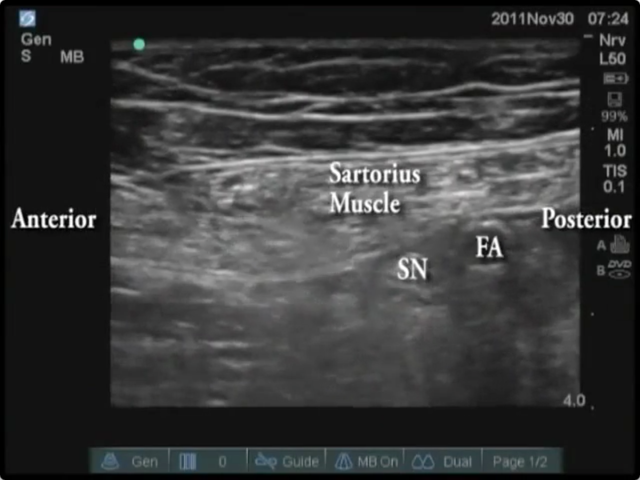

• 4: Ultrasound-Guided Mid-Thigh Saphenous Nerve Block

(NO AUDIO IN THIS VIDEO)

Block of the Day #4: Dr. Jeff Nabonsal from the Andrews Research & Education Institute performs this block in conjunction with a continuous popliteal sciatic catheter for postoperative analgesia following a triple ankle arthrodesis.